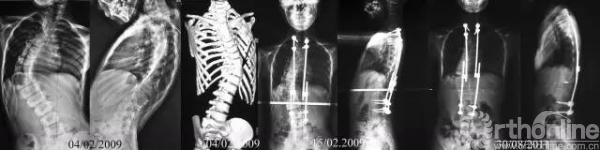

8岁患儿,先天性脊柱侧凸,侧凸弧累及胸段较长脊柱,呈进展性,畸形的发展将导致严重、僵硬的脊柱畸形,严重压迫心肺,影响患者生活质量甚至危及生命。而由于侧凸弧较长,早期的融合术会导致“短躯干”以及“胸廓发育不良综合征”。使用双生棒技术科在矫正畸形同时保留脊柱生长能力。患者术后2年随访,经历4次撑开术,矫形维持良好,心肺受压明显改善,脊柱纵向生长明显。